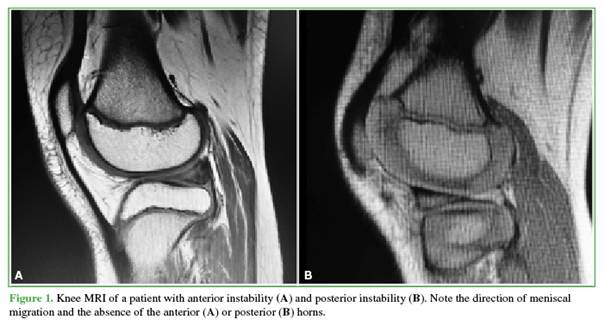

The tear pattern of the discoid meniscus is assessed using the hook probe, with particular attention to identifying peripheral instability. The hook is placed in the popliteal hiatus to apply traction to the posterior horn and confirm the degree of instability. If the tear site is easily accessible, meniscal repair is performed before saucerization to more precisely identify the areas of the meniscus that require resection. This approach is typically employed when there is anterior or posterior meniscal migration (Figure 1). If access is hindered due to the bulk of the discoid meniscus, which obstructs visualization of the lesion or area of instability, a limited central resection may be carried out first to improve exposure.